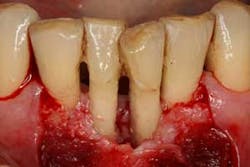

Figures 7a, 7b, and 7c: Osseous surgery in the mandibular anterior sextant with debridement of root surfaces and then regeneration.

Briefly, during osseous surgery, the upper right molars were treated with a combination of autograft and platelet-derived growth factor/Beta-tricalcium phosphate along with a porcine collagen graft (figures 5a and 5b). The upper left osseous surgery consisted of the same treatment (figures 6a and 6b), but also included the extraction of a hopeless tooth No. 15. Once again, the anterior osseous surgery consisted of the same regenerative materials as the former surgeries but with the addition of a porcine soft-tissue graft (figures 7a, 7b, and 7c). After the initial healing phase, the patient was placed on a strict home-care regimen and was seen every eight to 12 weeks for hygiene recare. The patient maintained excellent hygiene throughout the five-year follow-up period.